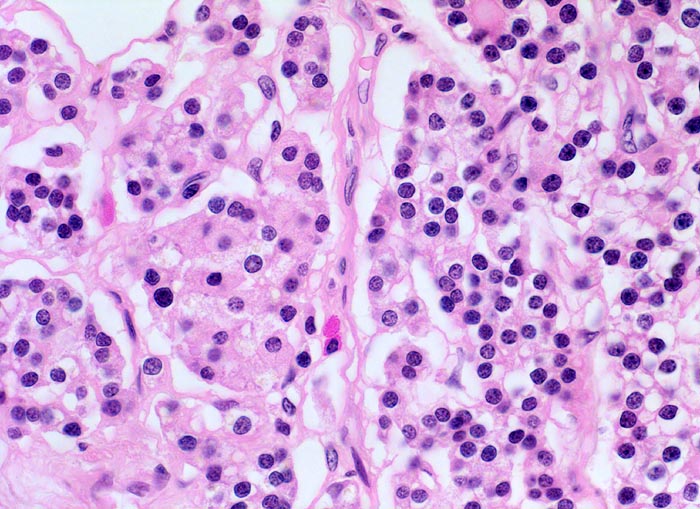

normale Nebenschilddrüse: Hauptzellen

Die Hauptzellen bilden das Parathormon. Sie enthalten basophile Granula, Glykogen und Lipide im Zytoplasma. Die Kerne sind rund, das Chromatin ist sehr dicht. Je nach Funktionszustand erscheinen Hauptzellen hell (glykogenreiche, wenig aktive wasserhelle Zellen) oder dunkel (aktiv).

Das Abschätzen der hormonellen Aktivität der Nebenschilddrüse und die Differenzierung in normal, hyperplastisch oder adenomatös aufgrund histologischer Kriterien allein ist schwierig. Drüsengrösse, Gewicht, Form und relatives Verhältnis von Fettzellen und Hauptzellen sollten bei der funktionellen Beurteilung berücksichtigt werden. Der Umstand, dass oxyphile Zellen in Adenomen und hyperplastischen Drüsen funktionell sind, nicht aber in normalen Drüsen muss berücksichtigt werden.